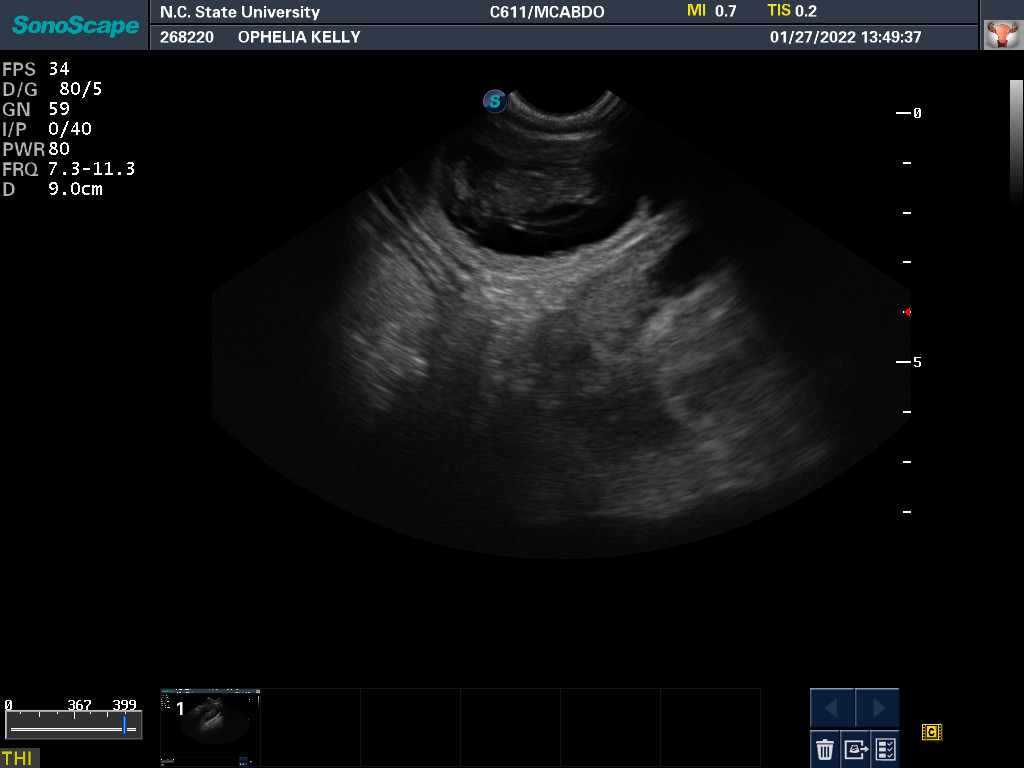

Ultrasound today by the theriogenology (reproduction) veterinarians at NC State University showed that Ophelia is pregnant with three puppies, possibly four puppies. (It can be difficult to accurately count puppies using ultrasound.)